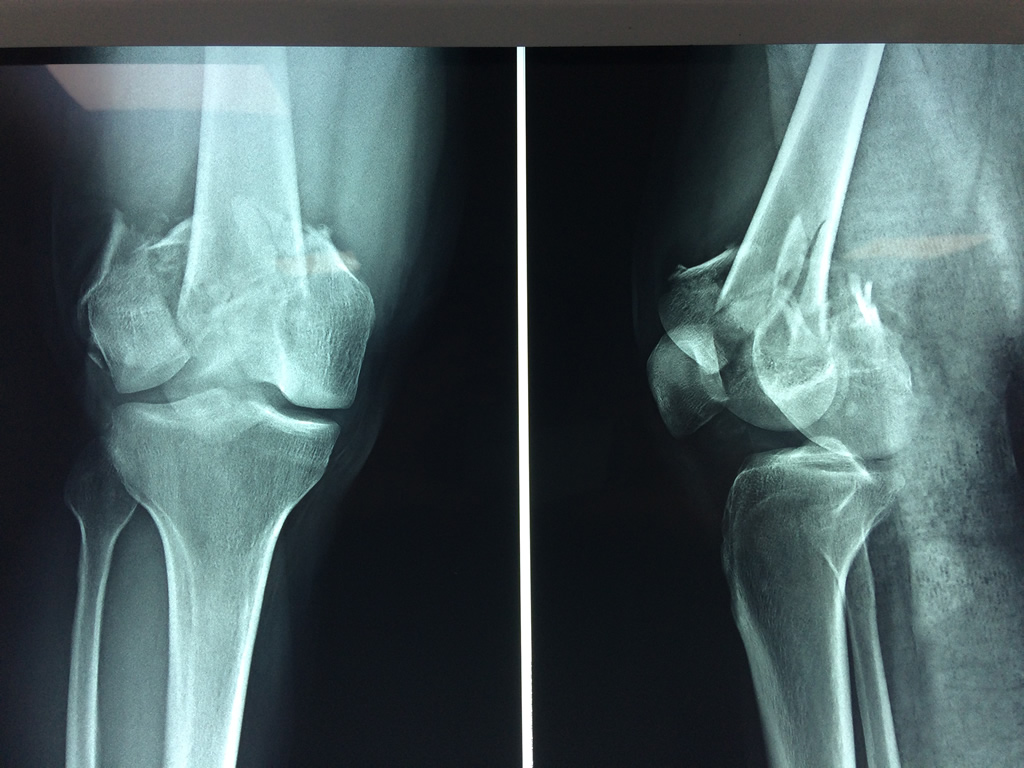

Cirugías de Peroné y Tibia